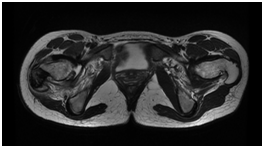

The simple x-ray showed a lytic lesion of the right greater trochanter with well-defined borders and no calcifications within it (Figure 1). The laboratory findings were characteristic of severe protein calorie malnutrition with a normal full blood count and CRP. The magnetic resonance imaging showed signal alteration at the right greater trochanter measuring 3.3 cm in diameter and triangular in morphology, with low signal in T1 and T2. It was well demarcated by a hypointense line and associated with bone marrow oedema of practically the whole of the right neck of femur. We also visualised significant signal changes with acute inflammatory characteristics of the tendons inserting into the right greater trochanter, related to acute tendinopathy in that region (Figure 2).

• Figure 2: MRI scan showing increased signal in the bone marrow and perilesional tendons.